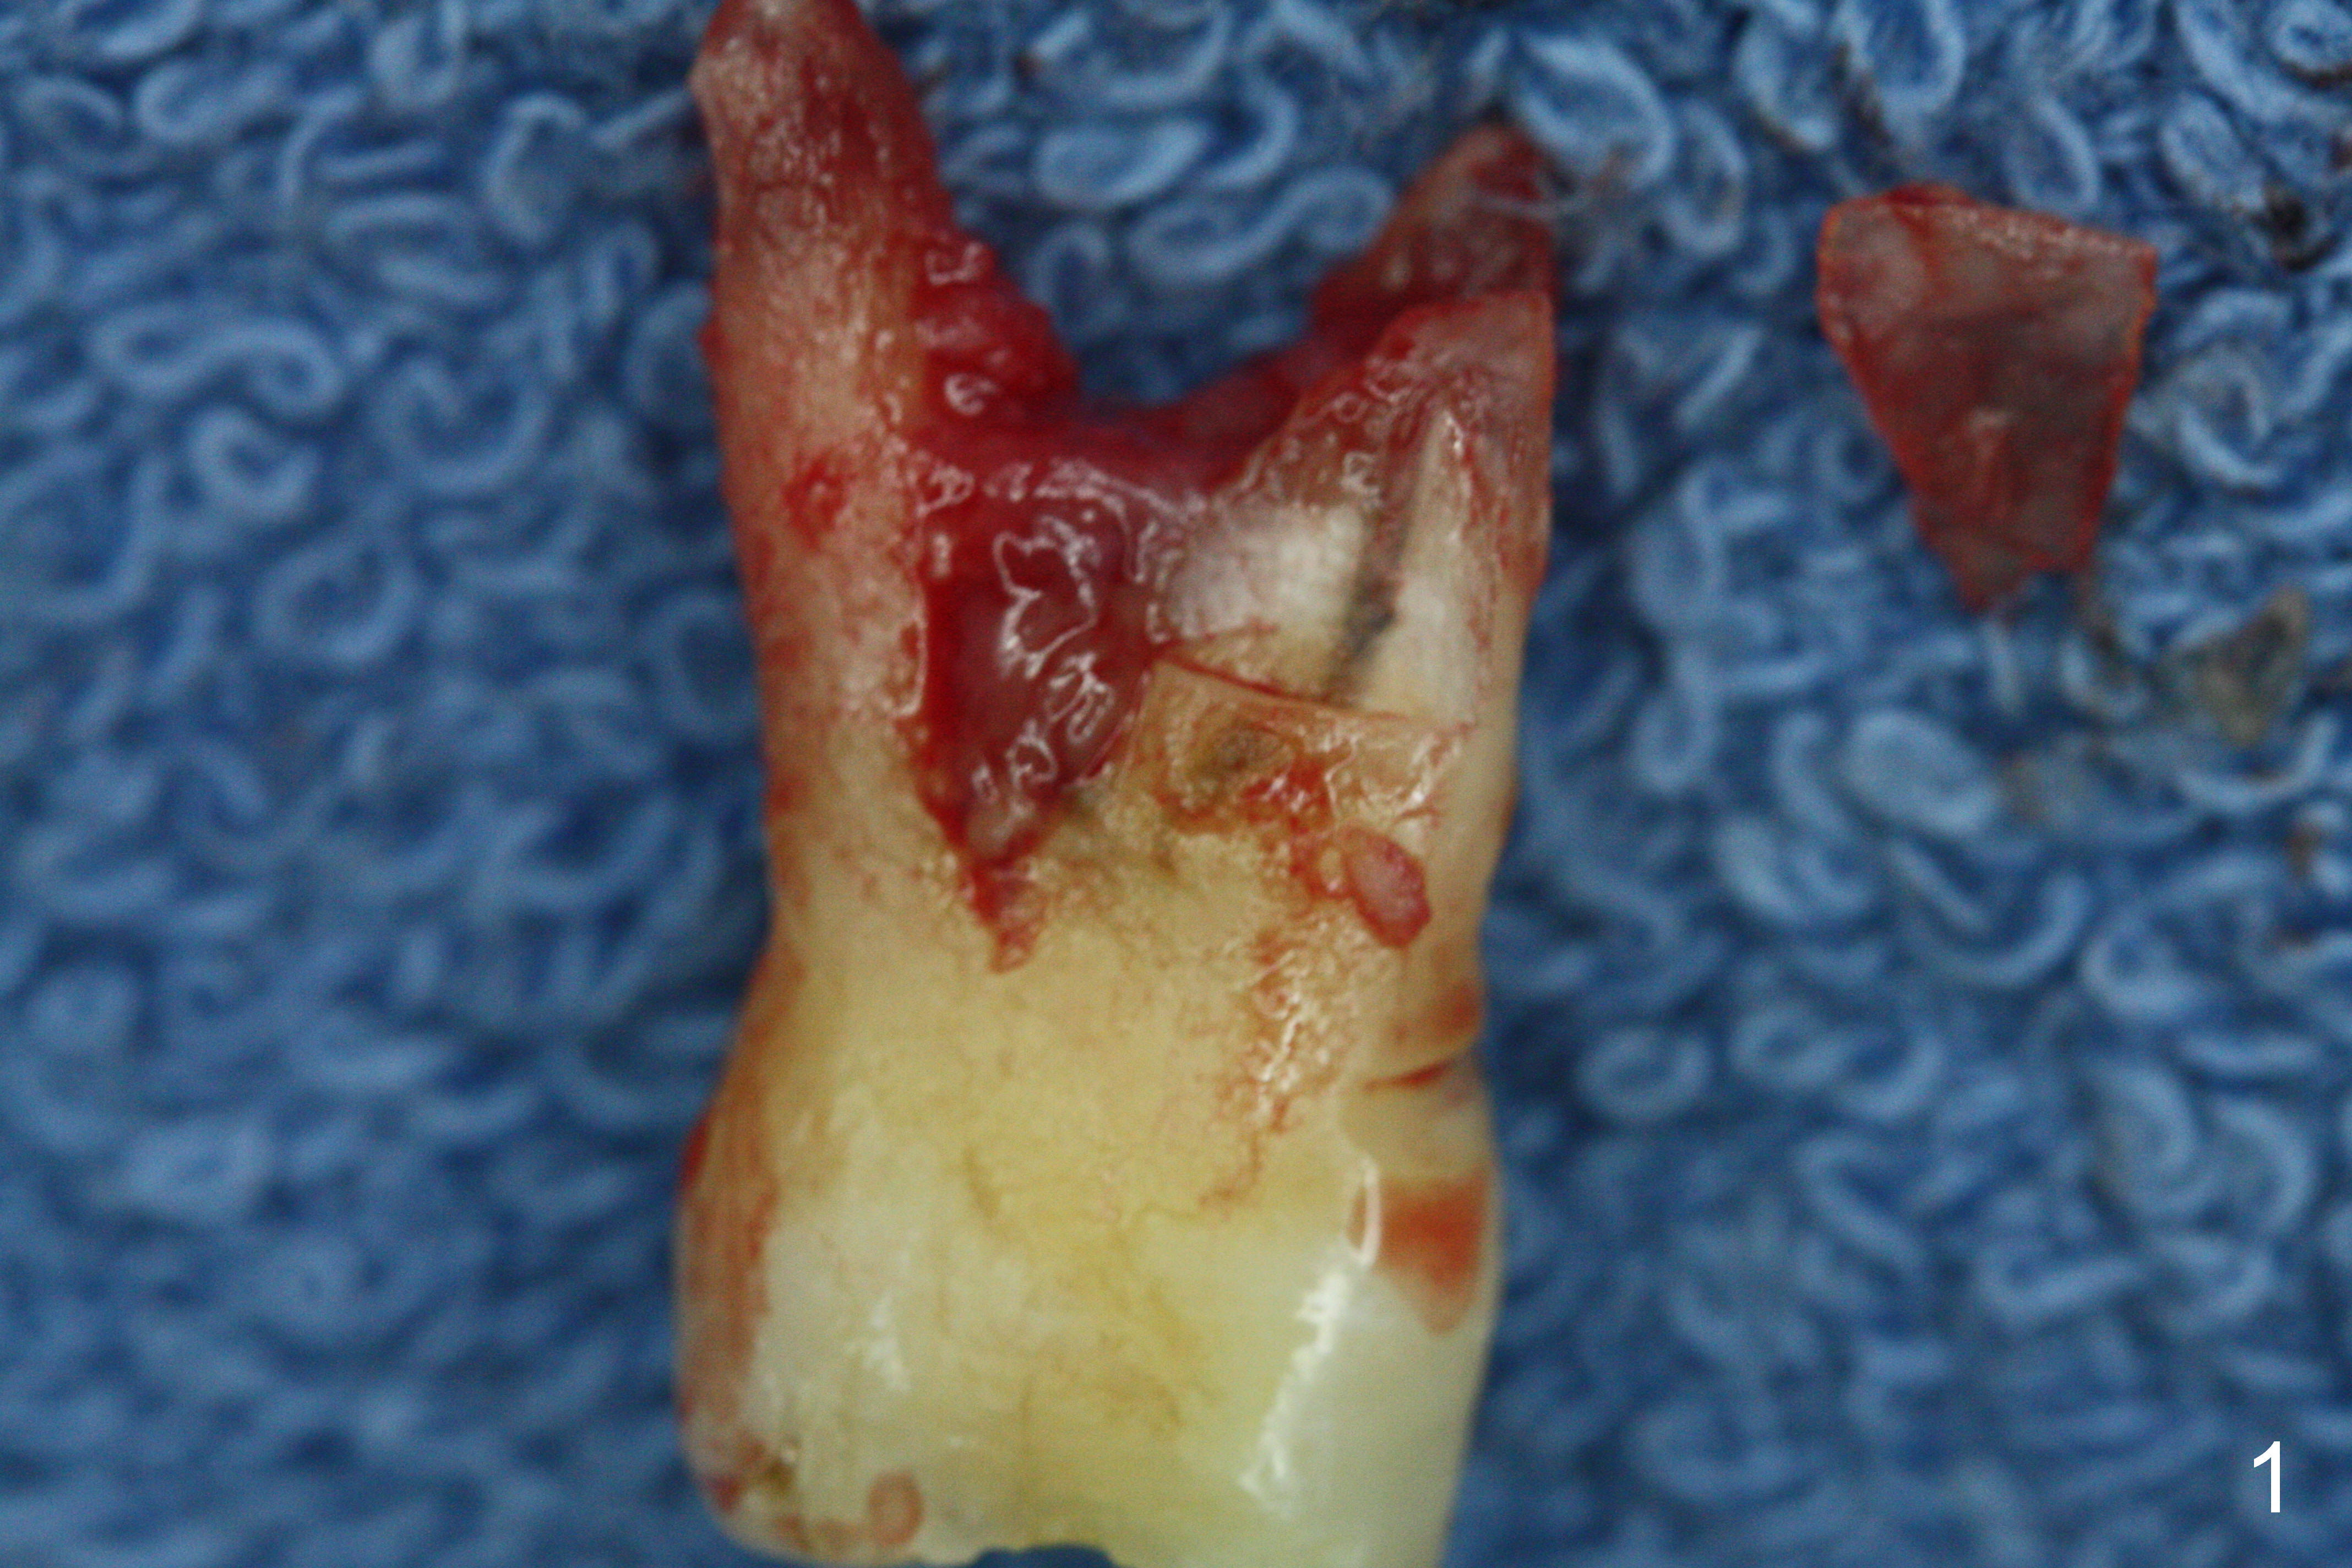

Preop exam show that the tooth #14 appears to be more severe than #18. When the former is extracted with forceps (not so easy), the mesial portion of the mesiobuccal root splits. The latter may be the reason for discomfort and one of the outcomes of advanced peridontitis. The septum is wide enough to use 4.3 mm Magic Drill (MD) following 1.6 mm pilot drill and Marking bur. A 5x13 mm IBS implant is placed apical to the mesial and distal crest and coronal to the septum (Fig.2,3). Insertion torque is ~ 35 Ncm. A 6.0x5.7(4) mm pair abutment is chosen over a 6.5 mm one, because the implant is placed somewhat distally (Fig.4,5). If the implant were placed more apically, the 4 mm cuff would be short for restoration. Allograft and autogenous bone harvested from the MD is placed around the coronal portion of the implant and the abutment cuff (*). Acrylic is spread around the abutment to hold the bone graft in place (without trimming).

The amount of the bone graft mesial and distal the implant seems to reduce 3 and 4 months postop, respectively (Fig.6,7 arrowheads). When the acrylic is cut off 4 months postop, the bone graft is loose. The gingiva is unhealthy. The abutment and implant are loose. A healing abutment is placed (5x4 mm). The implant is torqued to 35 Ncm 6 months postop with the healing abutment reapplied. The patient will return for follow up nearly 9 months postop. A larger healing abutment will be used if the implant is stable. Two weeks later, use a smaller restorative abutment for easy impression. In fact the implant is unstable with #15 mesial shift due to abnormal occlusion with #17 (Fig.8). Bone density around the implant is low (* in Fig.9 (PA), 10,11 (CT sagittal, coronal sections)). A healing screw is placed for self healing. A 2nd option is to remove the implant (Fig.12), BEB (Fig.13) and place the implant deeper (Fig.14) or larger one (5.5-6.5x13 mm). The 3rd option is to place larger and longer implants (Fig.15 (tapered), 16 (cylindrical)). The implant access has partially closed 14 months postop, but there is a small buccal opening with sanguine exudate. Incision reveals severe bone loss around the implant; the mobile tooth #15 is extracted (Fig.17). After debridement and irrigation with normal saline, Vera Graft (Fig.18 *) and Collagen plug are placed with periodontal dressing.